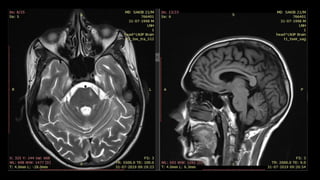

• #162 Here is an example of a young patient presenting with severe acute neck pain SHOWING left ICA dissection ON T2wi AS crescentric shaped hyperintense intramural hematoma causing expansion of the artery. However there is no narrowing of ICA lumen

• #163 Another example showing circumferential intramural hematoma seen bilaterally causing expansion of the bilateral ICA . There is narrowed lumen of the right ICA and open lumen of the left ICA